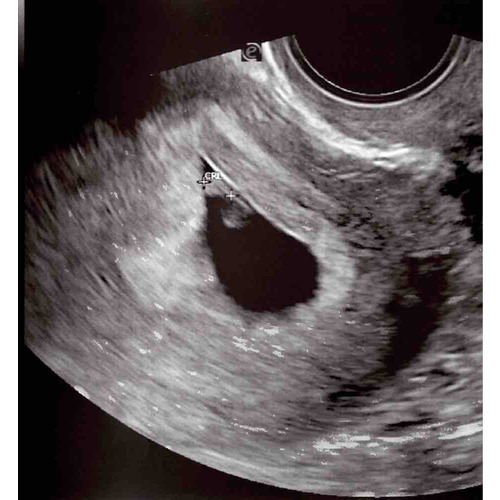

7+1 weken. Echo is inwendig gemaakt. Ben heel benieuwd want ik kan er zelf niks van maken 😅🥰

7+1 weken. Echo is inwendig gemaakt. Ben heel benieuwd want ik kan er zelf ...

💗